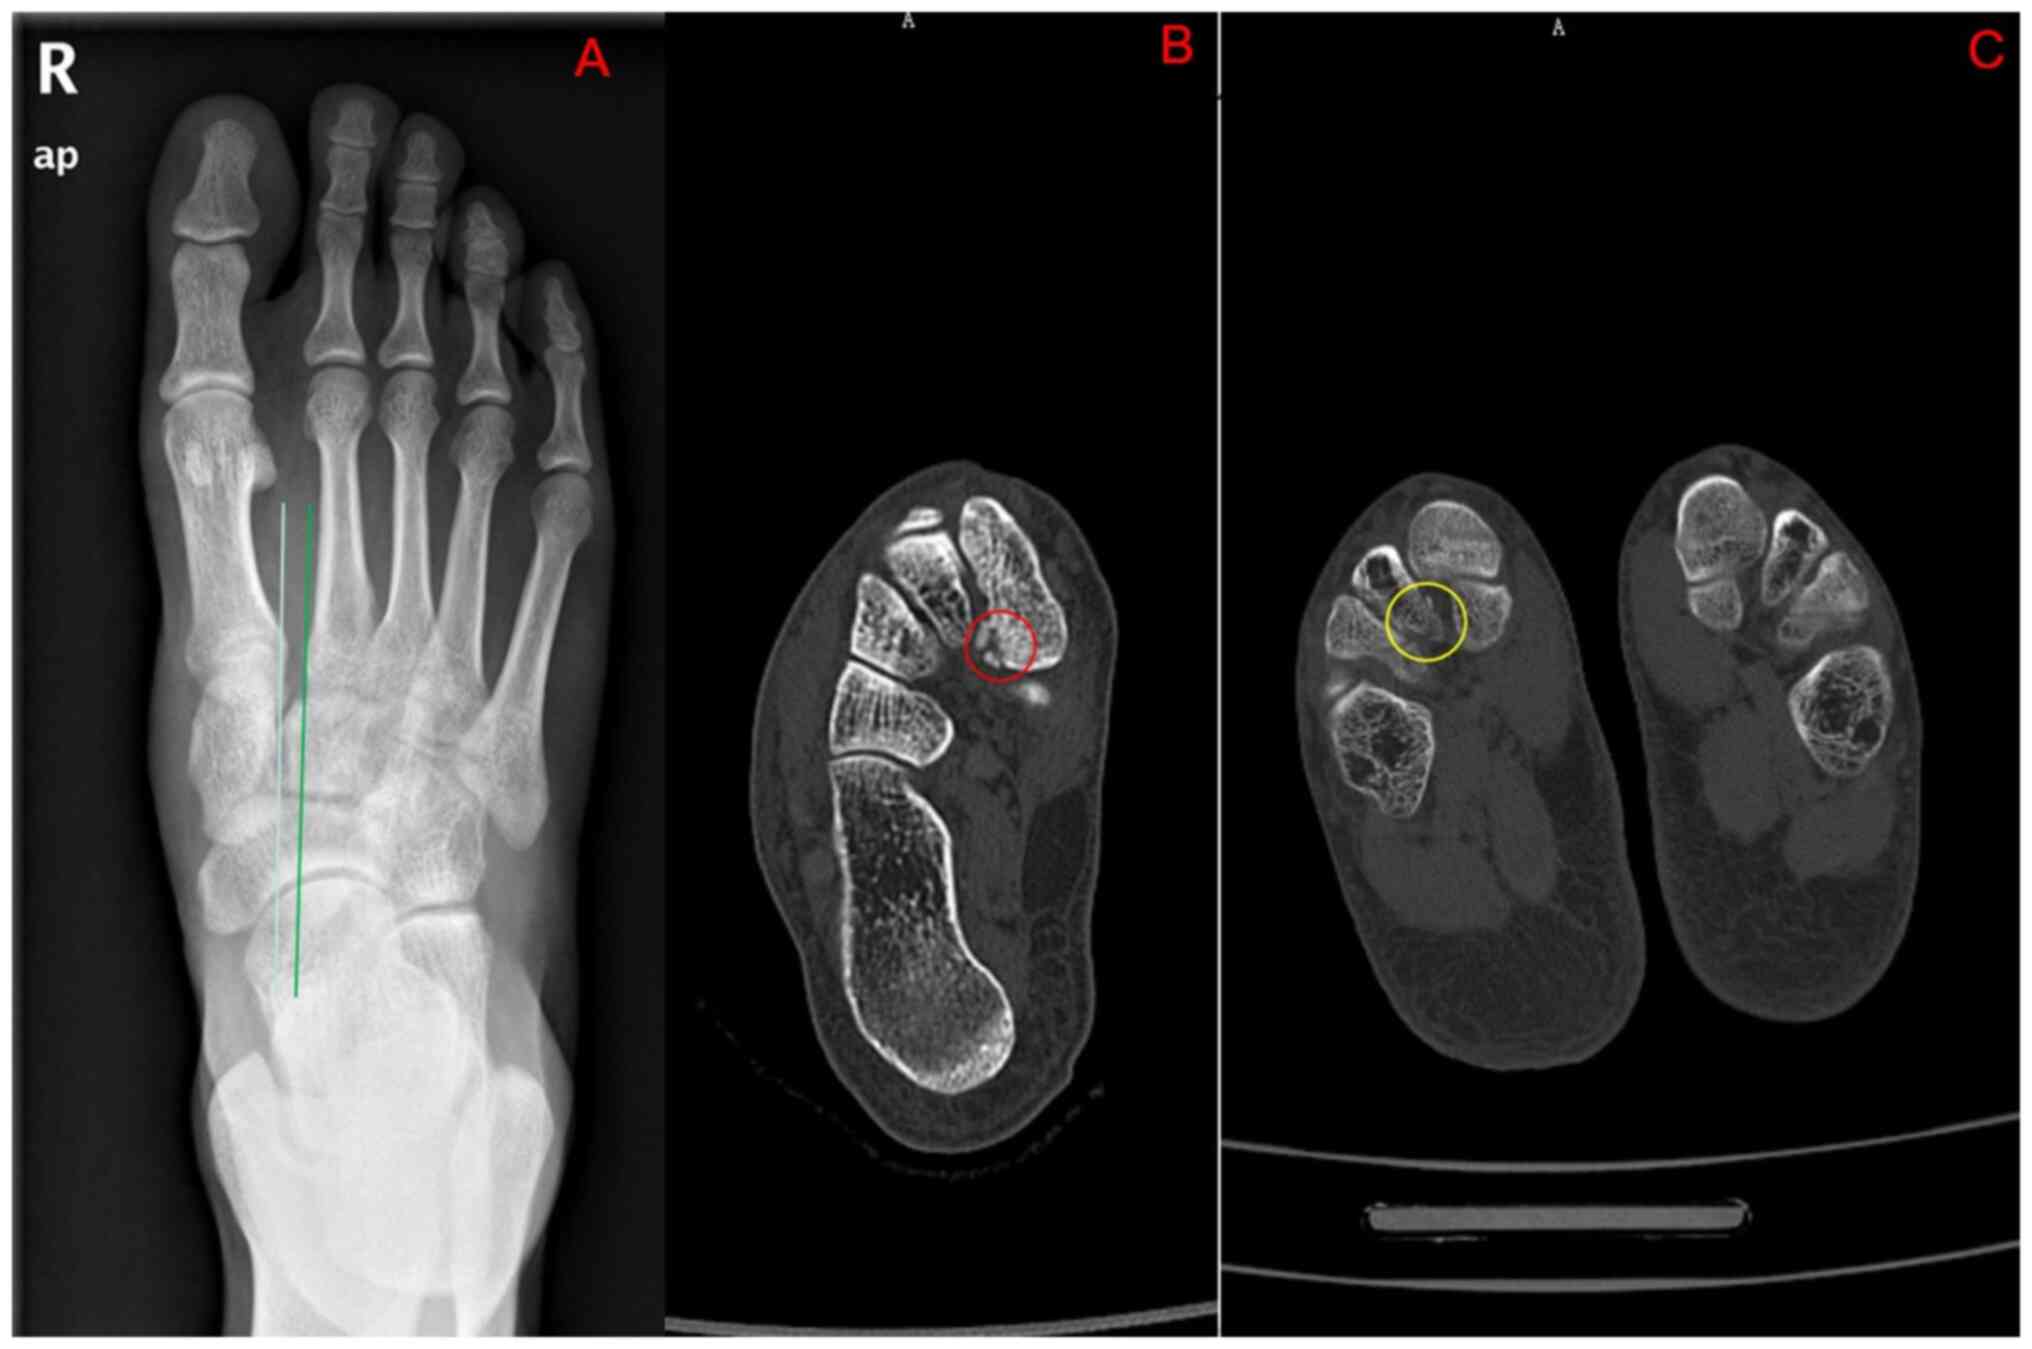

Comparison of diagnostic performance of X‑ray, CT and MRI in patients with surgically confirmed subtle Lisfranc injuries

The present study aimed to compare the diagnostic performance of three imaging tests: X‑ray, computed tomography (CT) and magnetic resonance imaging (MRI), for subtle Lisfranc injuries and three anatomical subtype injuries. The non‑weight‑bearing X‑ray, CT and MRI imaging results of patients with subtle Lisfranc injuries from September 2013 to March 2022 were retrospectively reviewed. Subtle Lisfranc injuries and three anatomical subtypes (first, second and cuneiform rays) were diagnosed based on the surgical reports. The diagnostic performance of X‑ray, CT and MRI was compared. The sensitivity (Sn), specificity (Sp), positive predictive value, negative predictive value, area under the receiver operating characteristic curve (AUC) and κ coefficient were reported. A total of 31 patients were included in the study. The correct diagnosis was made in 48.4% (15/31), 87.1% (27/31) and 96.8% (30/31) of patients by X‑ray, CT and MRI, respectively. A total of 54 different anatomical injuries were found intraoperatively in all patients, with MRI and CT having high agreement (Sn, 72.2 and 87.0%; κ, 0.69 and 0.78, respectively) and X‑ray having a low agreement (Sn, 29.6%; κ, 0.26) with the surgical findings. Regarding the first‑ray injuries, CT had the highest Sn (76.9%), Sp (100%) and AUC (0.885) in diagnosing subtle Lisfranc injuries. MRI showed the best Sn (88.5 and 93.3%, respectively) and AUC (0.942 and 0.904, respectively) in both second and cuneiform rays. In conclusion, non‑weight‑bearing X‑rays had poor diagnostic accuracy for subtle Lisfranc injuries and their subtypes. CT was superior to X‑rays and MRI in diagnosing first‑ray injuries. Although not significantly different from CT in terms of overall diagnosis, MRI was superior to X‑ray and CT in diagnosing second and cuneiform‑ray injuries.

Figure 1